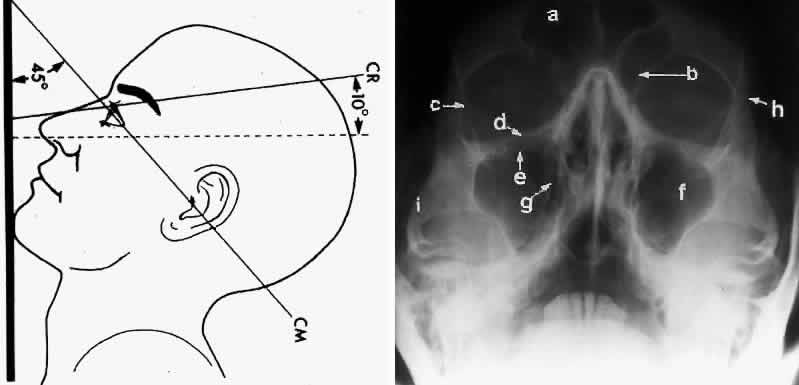

In an attempt to improve the visualization of the maxillary and ethmoid sinuses, in 1915 Waters and Waldron7 described a radiographic projection (Fig. 2) that eliminated the overlapping shadows of the dense petrous ridge of the temporal bone. Waters projection is created by placing the chin of the patient on the x-ray cassette with the canthomeatal line (the line that connects the lateral canthus and the external auditory meatus) at 37 degrees to 45 degrees.5,6 This orientation is accomplished if the nose of the patient is approximately 0.5 to 1.5 cm above the x-ray plate.7,8 A mnemonic is—the patient raises the chin up to sip water.

Fig. 2. A. Schematic showing positioning for a Waters projection. (CM, canthomeatal line; CR, central ray) B. Radiograph of a Waters projection. The petrous ridge lies below the maxillary sinus. (a, frontal sinus; b, medial orbital wall; c, innominate line; d, inferior orbital rim; e, orbital floor; f, maxillary antrum; g, superior orbital fissure; h, zygomatic-frontal suture; i, zygomatic arch) (A; Rao VM, Gonzalez CF: Plain film radiography and polytomography of the orbit. In Gonzalez CF, Becker MH, Flanagan JC [eds]: Diagnostic Imaging in Ophthalmology, pp 1–7. New York, Springer Verlag, 1986)

Waters view provides the best image of the maxillary antrum and good images of the orbital rim, orbital floor, zygomatic bones and arches, lesser wing of the sphenoid, and infraorbital foramen. This view is useful to the clinician in orbital floor fracture assessment because of the clear image of the orbital floor and the underlying maxillary sinus. The floor of the orbit should form a continuous radiographic line with the lateral wall of the orbit. Confusion can occur regarding the location of the orbital floor and its relationship to the orbital rim. The orbital floor is located inferior to the orbital rim not in the same plane, because of the orientation of the patient's head in Waters projection. A soft tissue density in the roof of the maxillary sinus or opacification of the floor of the sinus suggests an orbital floor disruption.